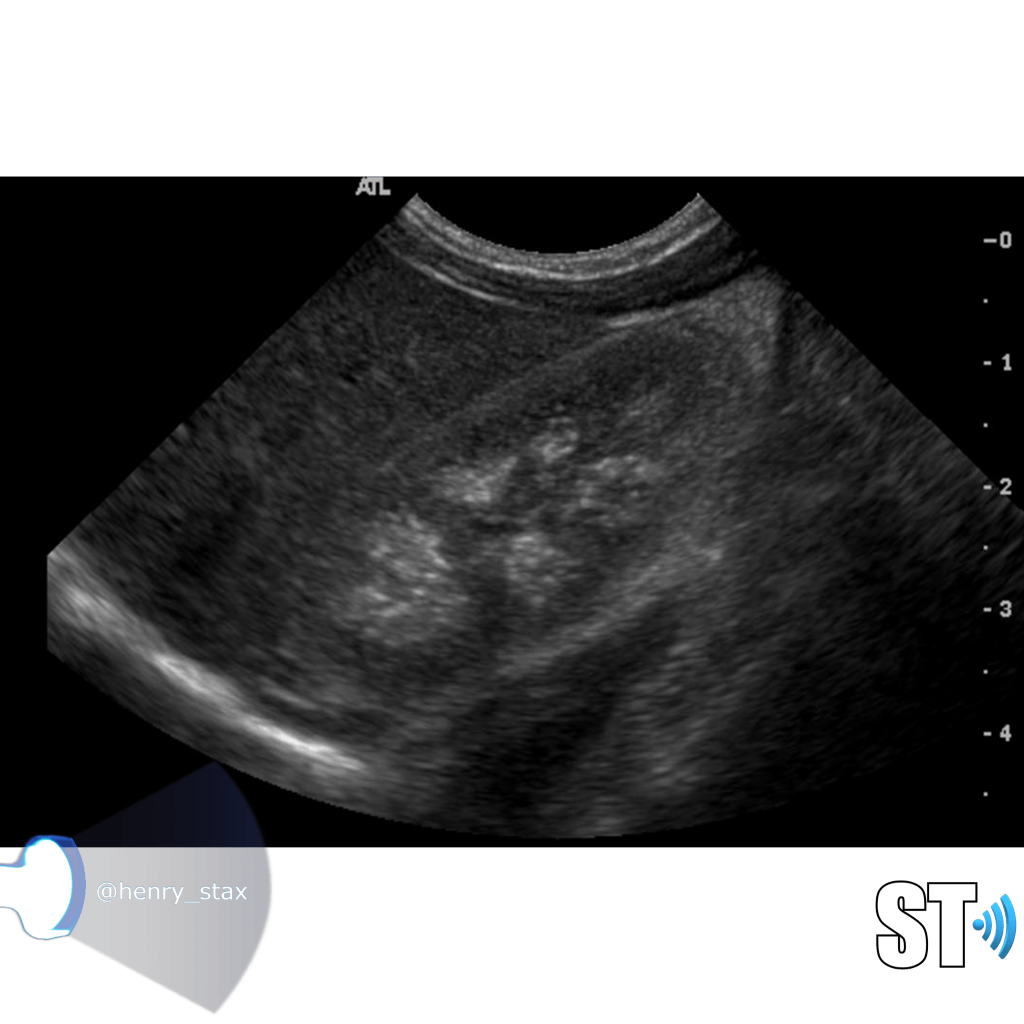

Renal Echogenicity

Another ultrasound sign of disease is echogenicity. Increased echogenicity is when the parenchymal echoes are greater than the liver. Usually the kidney is hypoechoic to almost isoechoic to the liver. Many different entities can cause increased echogenicity, that’s why when a radiologist reads an ultrasound with hyperechoic kidneys they usually attribute it to “medical renal disease”. A very hypoechoic kidney is also not normal, especially when it is focal as this could be due to infarction or infection.

The echogenicity of the kidney is just a single data point along with clinical and other laboratory findings a clinician can use in diagnosing renal disease.

For our purposes we need to tell whether the kidneys are hyperechoic or not, also is the corticomedullary (cmd) differentiation preserved or is it lost, this can give you clues as to the chronicity of renal parenchymal disease. If the cmd is easily seen it may suggest a more acute process, whereas chronic disease will usually show echogenic and atrophic kidney with little to no differentiation of the cortex to medulla